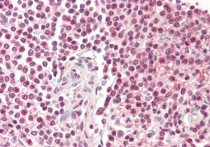

ARG63633 anti-Pirin antibody IHC-P image

Immunohistochemistry: Paraffin-embedded Human liver tissue. Antigen Retrieval: Steam tissue section in Citrate buffer (pH 6.0). The tissue section was stained with ARG63633 anti-Pirin antibody at 5 µg/ml dilution followed by AP-staining.